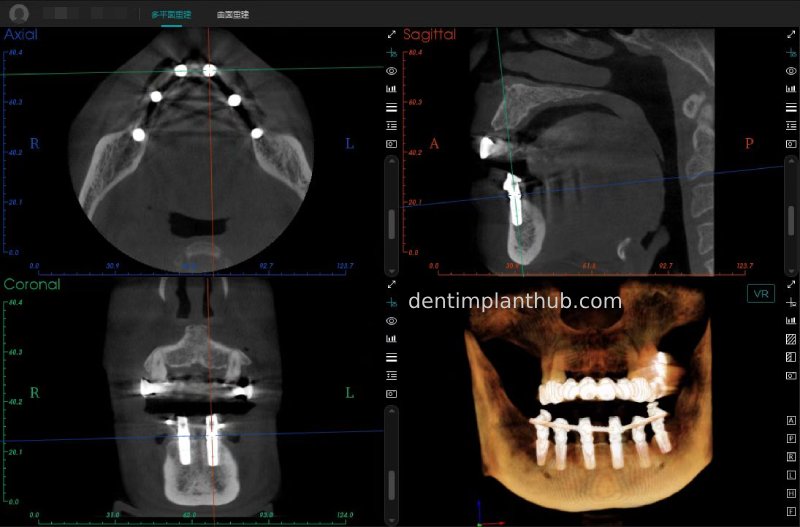

CBCT review results on 13 May '24

46

44

42

32

34

36

Maxillary condition as shown by CBCT on 13/5/24

16

14

12

22

24

26